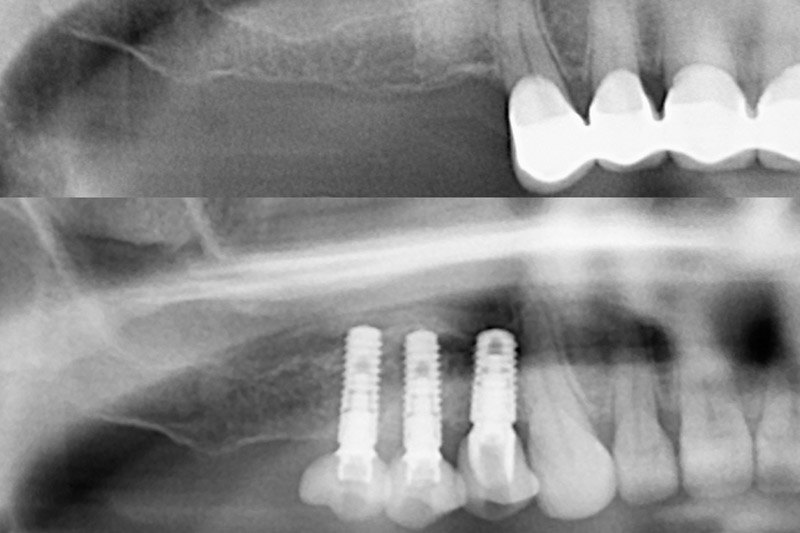

Wenn Zähne längere Zeit fehlen, kommt es zu einer Knochenresorption des Kieferkammes in Breite oder Höhe. Werden dann Implantate gewünscht, kann es sein, dass ein Knochenaufbau nötig wird.

Hierbei gibt es verschiedene Techniken wie Grafting, Ridge Splitting oder Sinuslift. Ist jedoch noch ein geringer Teil von Knochen vorhanden, besteht die Möglichkeit von Kurzimplantaten. Um die Möglichkeiten dieser Therapien abzuschätzen ist eine genaueste Diagnostik wichtig.

Wenn Zähne längere Zeit fehlen, kann es dadurch bedingt zu einer Knochenresorption kommen. In weiterer Folge kann es sein, dass zu wenig Knochen für ein Implantat vorhanden ist. Oft werden dann aufbauende Operationen wie Knochenerweiterung oder Knochenaufbau nötig.

Manchmal kann es jedoch auch sein, dass noch genug Knochen vorhanden ist und man sich diese zusätzlichen Operationsschritte erspart. Lassen Sie sich bei einem Beratungsgespräch über die Möglichkeit von Kurzimplantaten beraten.